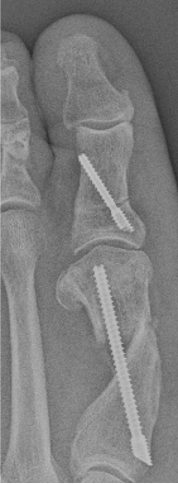

Another discussed complication not yet reported in the literature is latent dorsiflexion displacement of the head of the first metatarsal (LDDH). This can occur once weight-bearing starts, but is often seen after 6 weeks when the patient is back into regular shoe gear. While it may be asymptomatic, the symptomatic patient will complain of a dorsal bump, lesser metatarsalgia, and joint stiffness (Figures 6 A, B, C, D). Author EB has only seen this occur when using a single-screw technique. The authors believe this complication can be reduced with the use of a 2-screw construct to prevent instability. Further research into LDDH is necessary to avert these types of malunions.